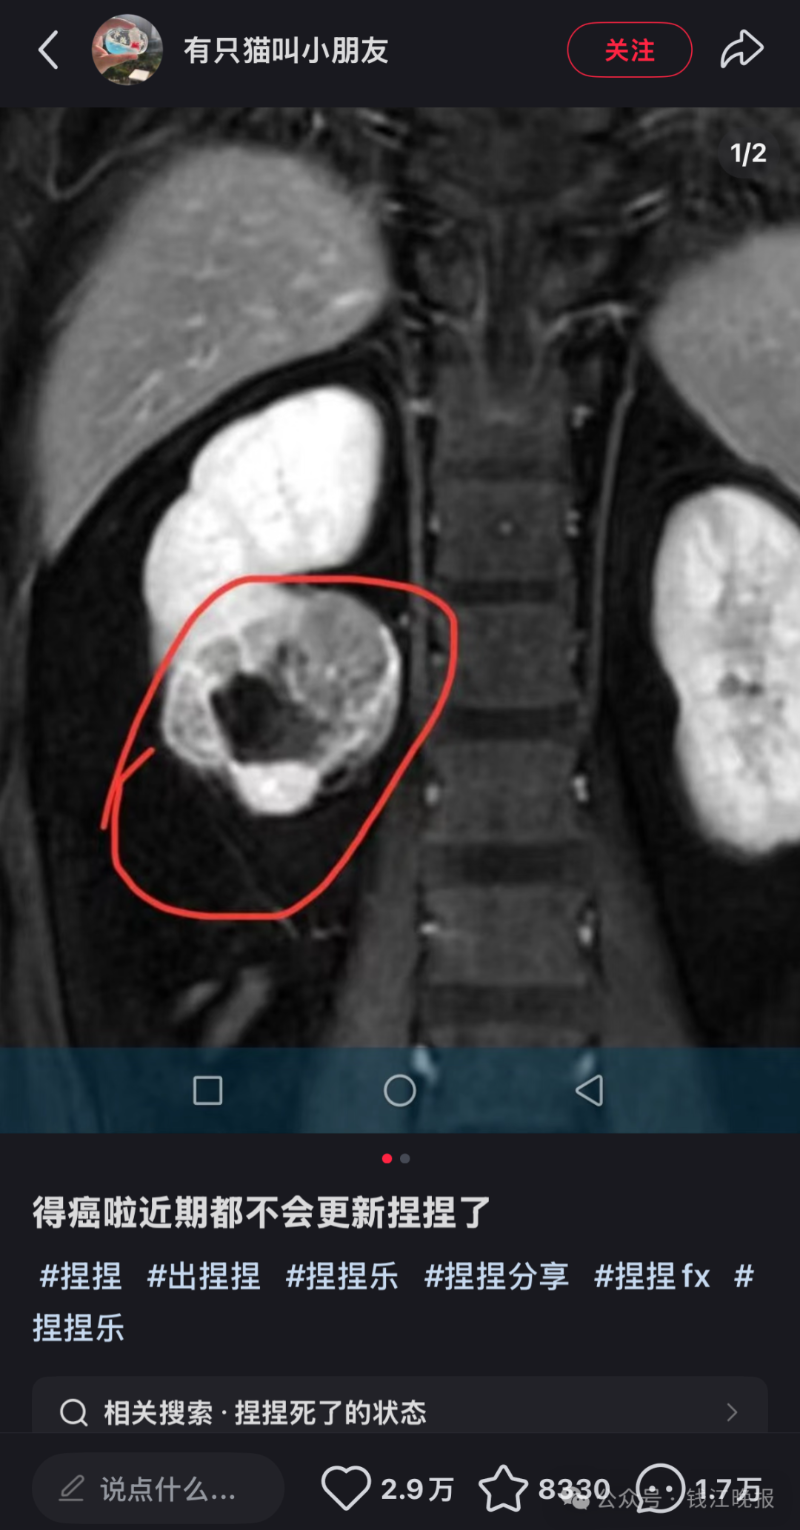

据深圳新闻网报道,该博主在社交媒体上发文透露自己罹患癌症,并宣布将暂时停止更新与“捏捏”玩具相关的视频内容。

该博主在社交平台宣布罹患癌症。图源其账号截图